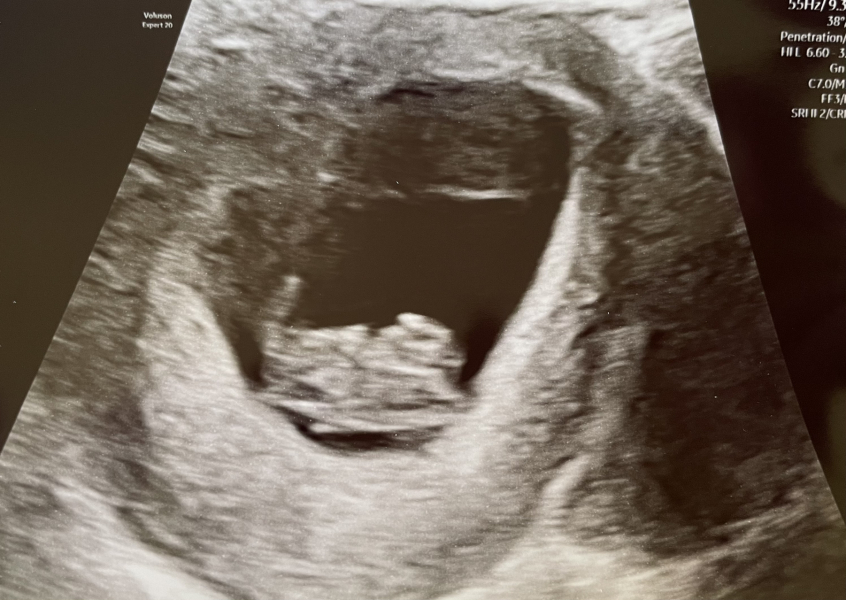

KittyFantastica · 24/07/2024 10:42

Heya @4LeafCloverBaby We did and things are looking hopeful 🤞 I keep waiting for relief to hit, but it just doesn't come. The pictures weren't great and that worried me too as I was thinking it should look a bit baby-like at nearly 9 weeks, but it just looked like a blob 😆

They very much still look like prawns at 9 weeks!

Hahaha, this one looks a bit like a bat @AppleTree16 That really made me laugh!